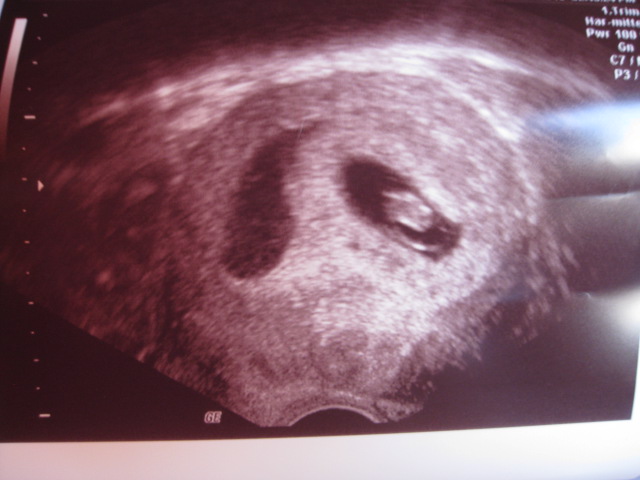

US zeigte mir das schlagende Herzchen, unglaublich

und wie das Kleine schon gewachsen ist, Wahnsinn

also alles bestens und ich bin erst mal beruhigt

PS: ich stell mal ein Bildchen rein

@RedAngel. tolles Foto und schön das es gut weitergeht.

Das Foto allerdings irritiert mich auch etwas...kannst du es beschreiben ?